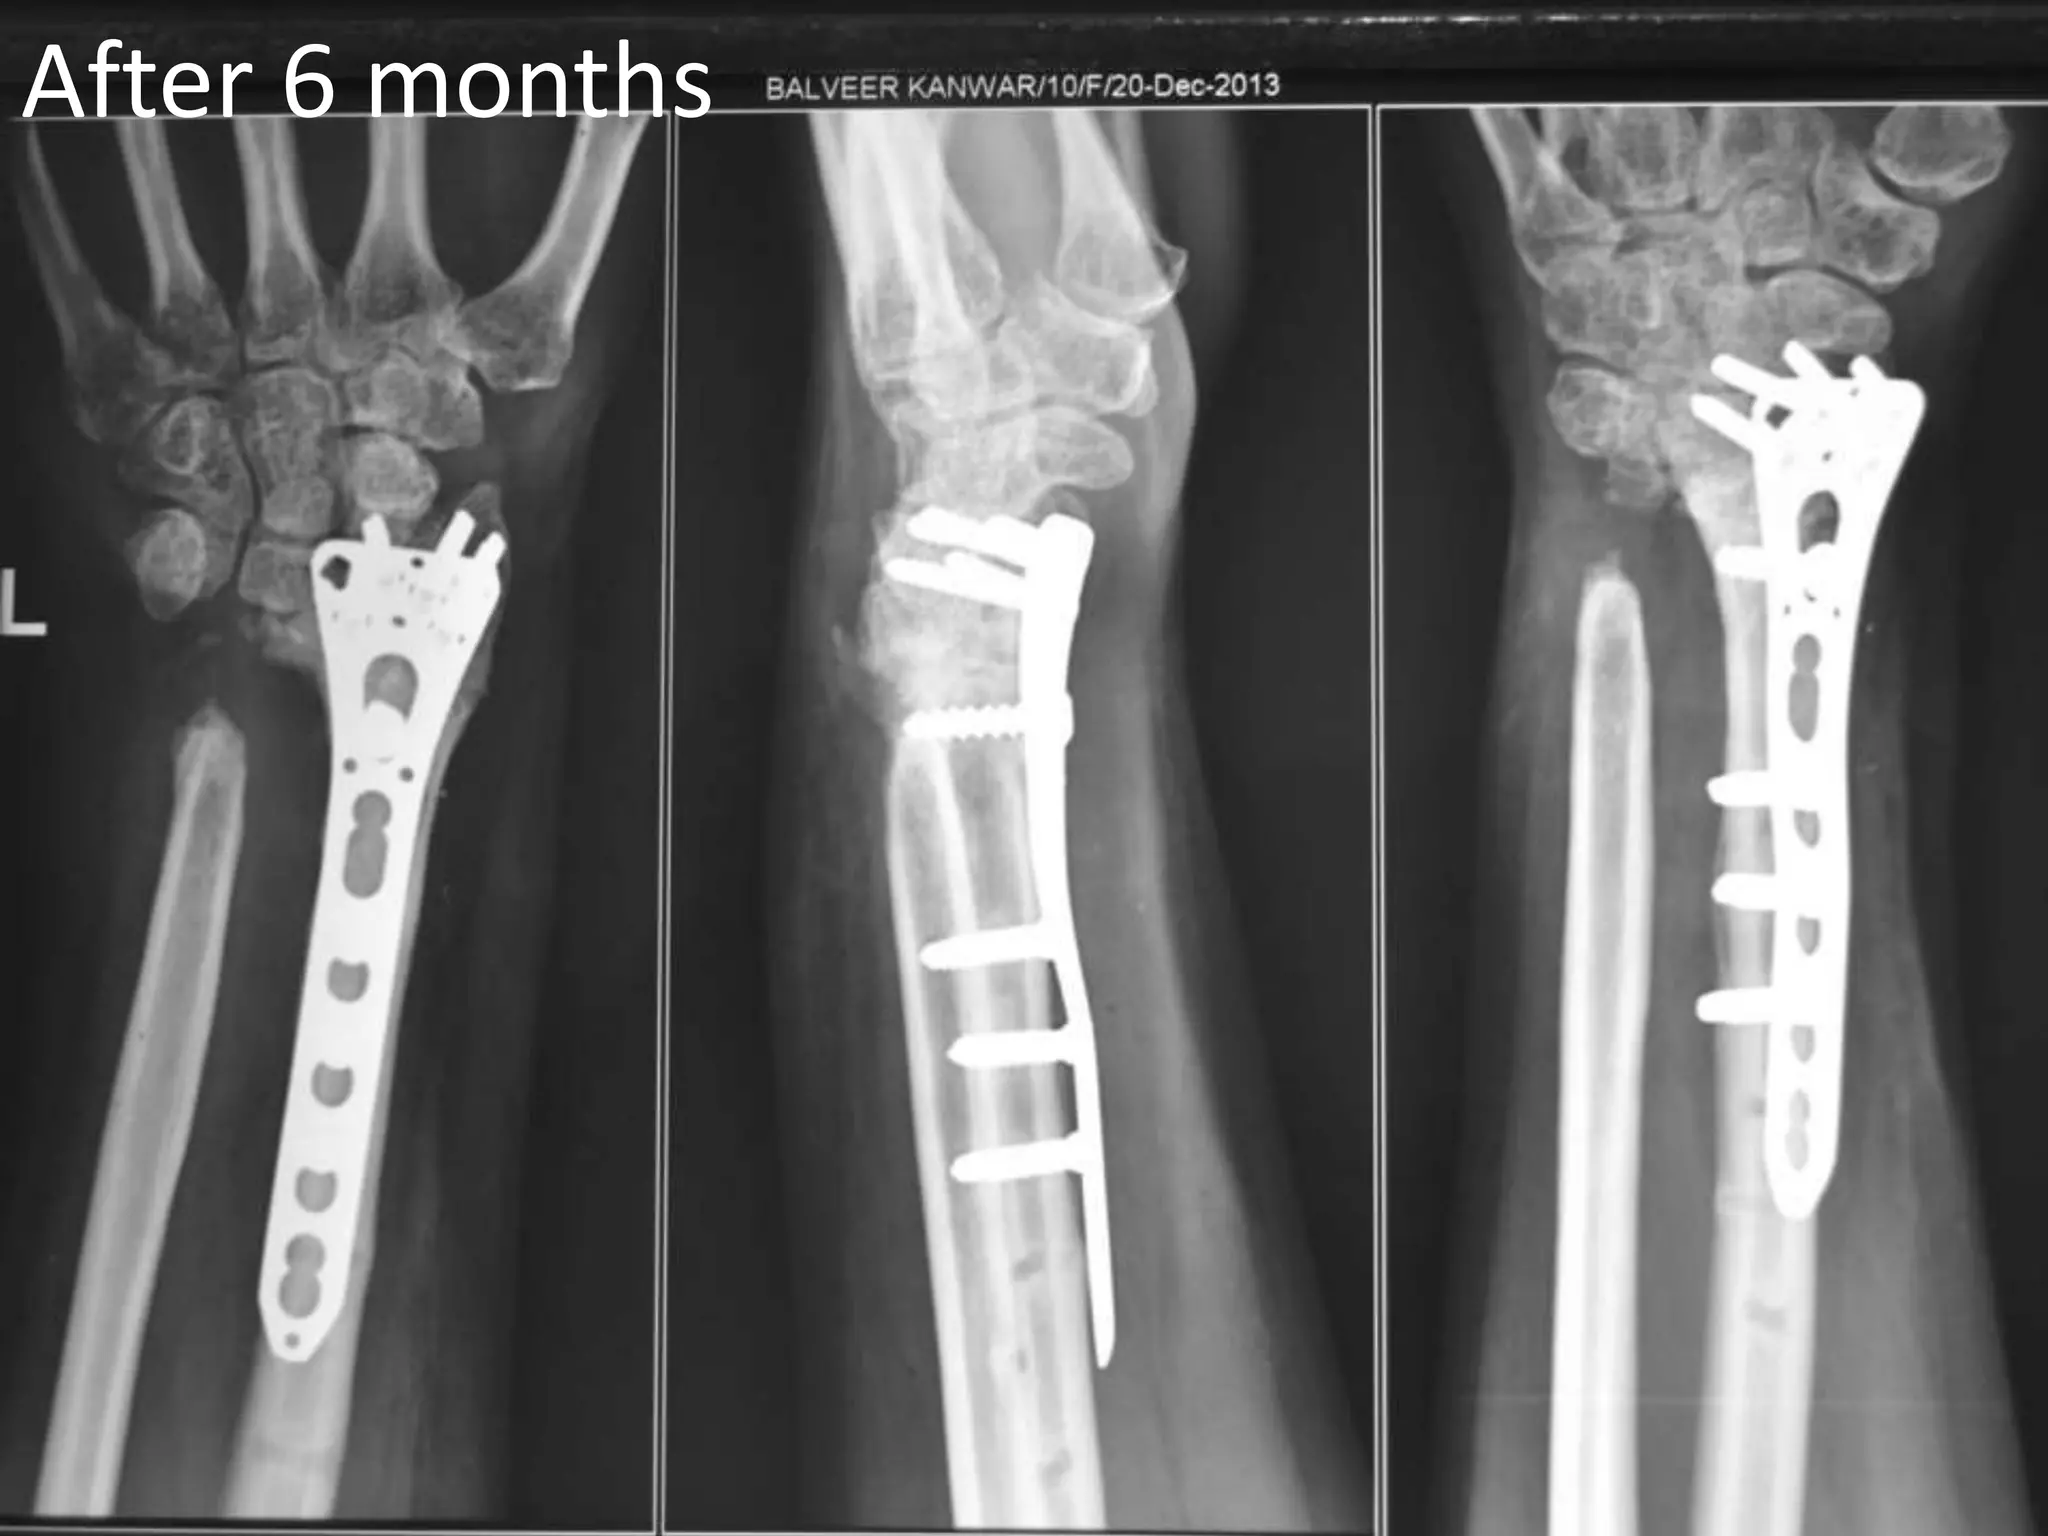

After 6 months

Oct 2013 10weeks Post surgery MP joint flexion ↑ Ex-fix removed Physio-continue Patient’s satisfaction good Wrist mobilization started.